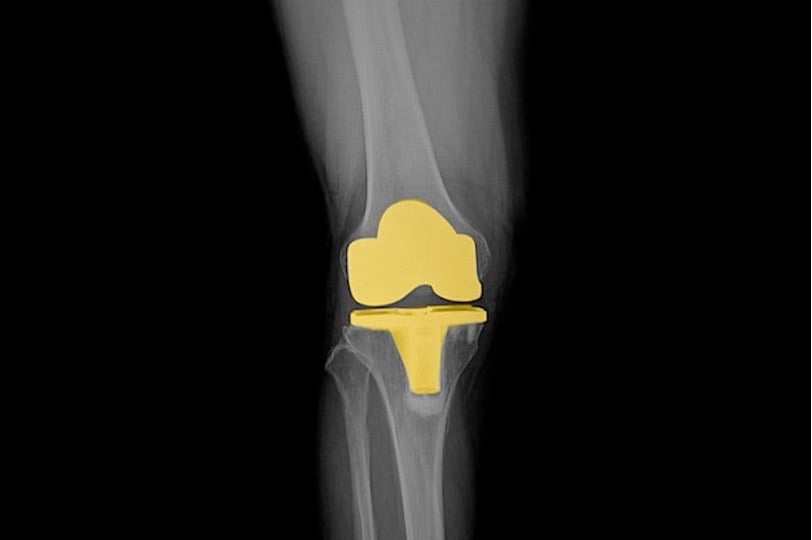

Knee osteoarthritis is one of the most common chronic conditions in orthopaedics, with total knee arthroplasty (TKA) being the gold-standard intervention for end-stage cases. There is growing interest in different tibial baseplate fixation methods in younger patients. This study aimed to compare long-term outcomes and survivorship of cemented tibial components, pegged porous cementless tibial components, and tantalum monoblock porous tibial components.

224 patients with knee osteoarthritis were randomized to receive different tibial baseplate fixation methods during total knee arthroplasty (TKA). The patients were assigned to three groups: Group 1 received a cemented tibial component (n=97), Group 2 received a pegged porous cementless tibial component (n=87), and Group 3 received a cementless tantalum monoblock porous tibial component (n=90). The primary outcome of interest was survivorship, and secondary outcomes included functional measures (such as the Oxford Knee Score & Knee Society Score) and radiological data. Outcomes were assessed up to 10 years postoperatively.

Irrespective of the tibial component, functional and radiological outcomes remained similar for up to 10 years post-operation.

Survivorship was excellent across all groups (99.6%).

Differences in functional outcomes were not statistically significant between groups.

Radiological and survival outcomes were similar in all three groups.

Bottom line. The study suggests that the long-term outcomes and survivorship are likely to be satisfactory in patients undergoing total knee arthroplasty, regardless of the choice of tibial component. Up to 10 years, the fixation method may not significantly impact the 10-year outcomes.